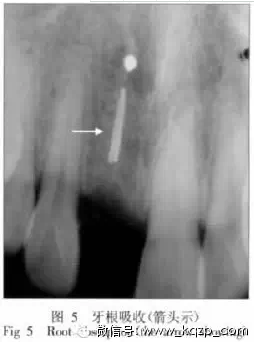

3.5 根管內(nèi)器械分離

在根管預(yù)備過程中,無論使用不銹鋼根管銼,還是鎳鈦根管銼,都會發(fā)生器械在根管內(nèi)分離的情況。Iqbal等[8]發(fā)現(xiàn),磨牙發(fā)生器械分離的幾率是前磨牙的2.9倍;根尖1/3處發(fā)生斷針的幾率是根管冠方及根中1/3處的6倍。但是,斷針在牙片上表現(xiàn)出來的阻射情況,有時和根管充填物密度非常接近,特別是當(dāng)斷針和根管充填物連接在一起時,兩者更難分清,這就需要進(jìn)一步觀察根管充填的密合度和根管邊緣的自然彎曲情況(圖6)。